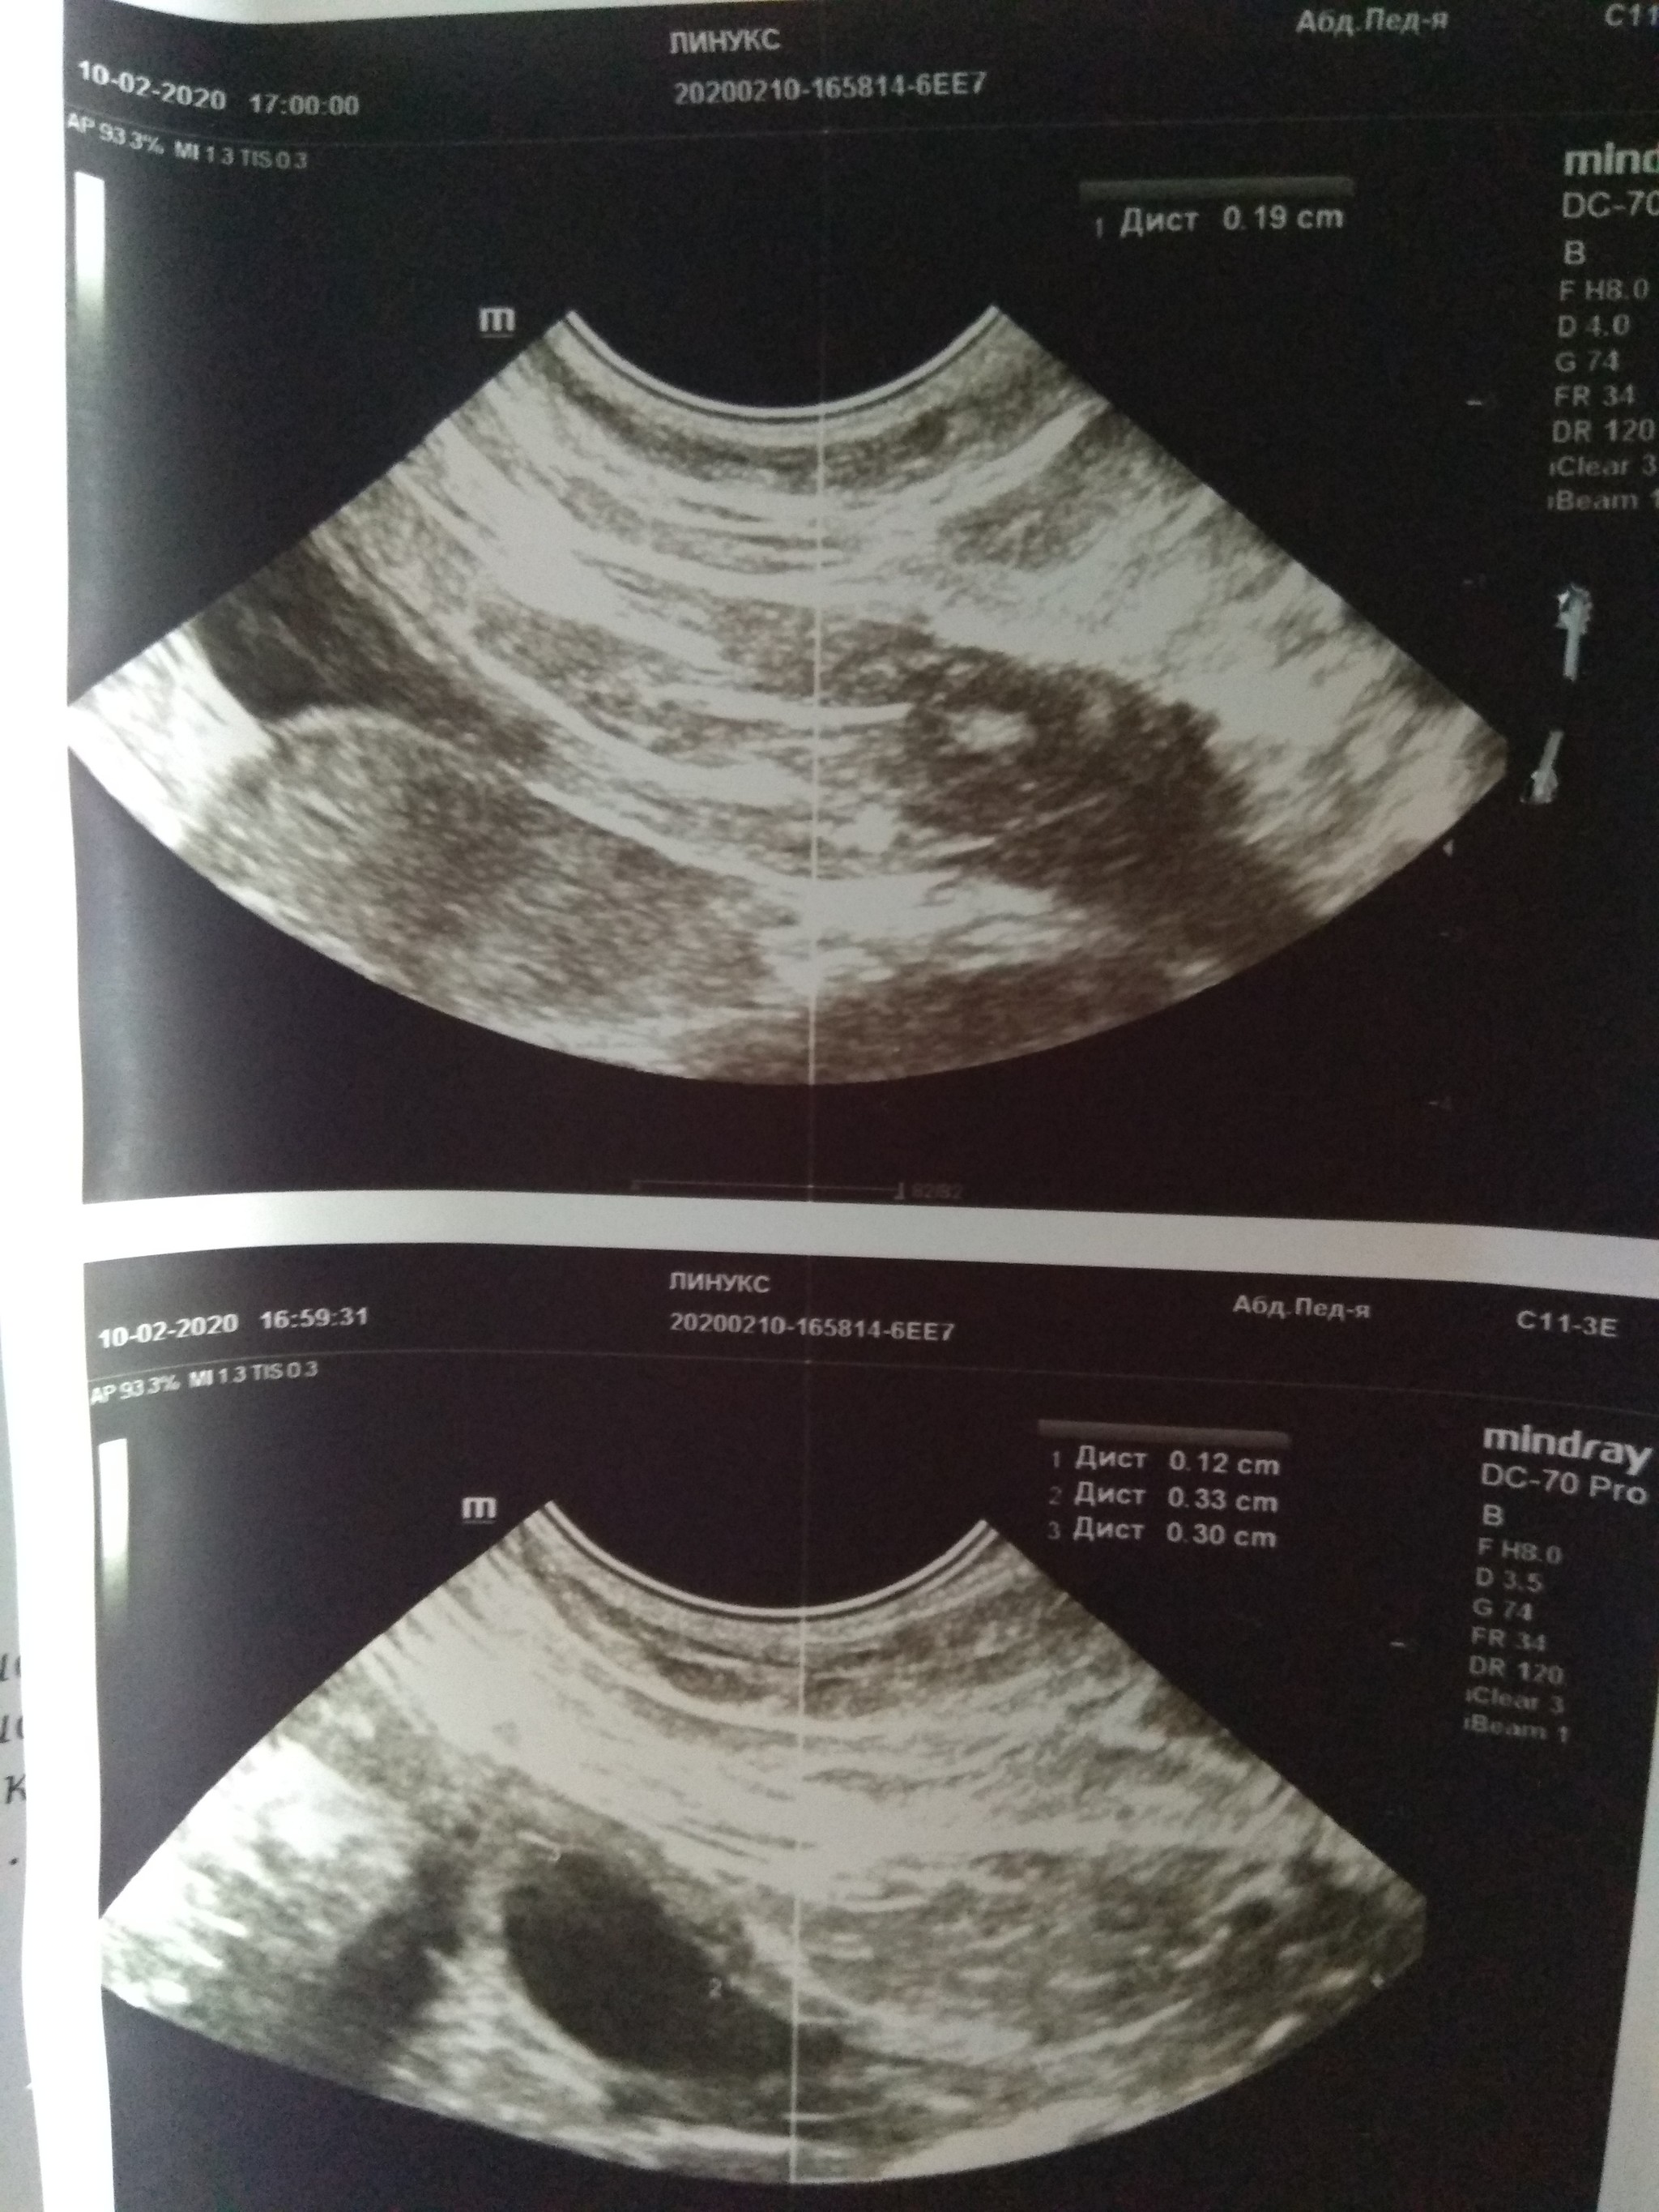

Пока люди отвернулись, Линукс порвал сетку, вышел погулять на карниз и превратился в ракету класса "окно-асфальт". Жив, цел, орёл, месяц ходил со спицей в лапе, и всё равно умудрялся буянить по ночам.